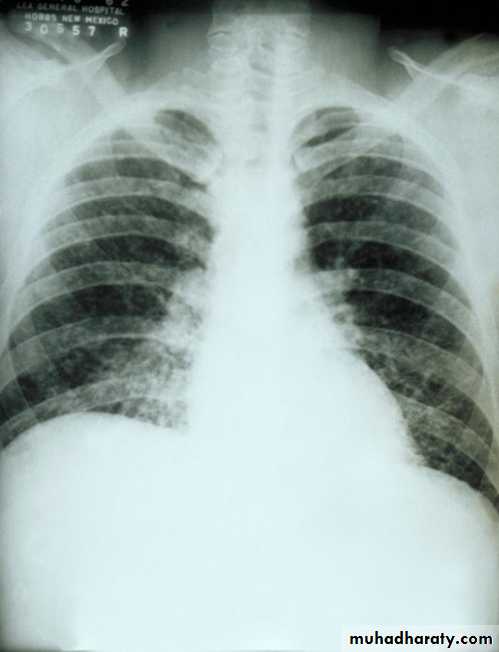

Clinical features

-incubation period of 1–3 days,

-fever, malaise and cough. May followed by Viral pneumonia.

- superinfection with Strep. pneumoniae, Staph. aureus or other bacteria

Complications

extrapulmonary manifestations include:

• myositis, myocarditis, pericarditis• neurological complications (Reye’s syndrome in children, encephalitis or transverse myelitis, fit).